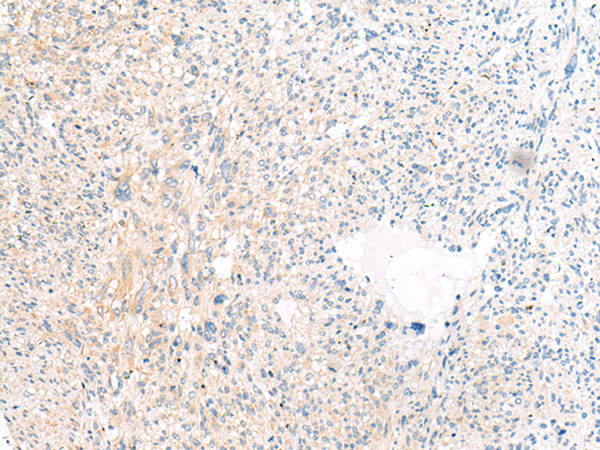

分类: 科研抗体货号: P11241别名: ALL; CML; PHL; BCR1; D22S11; D22S662应用: IHC反应种属: Human, Mouse